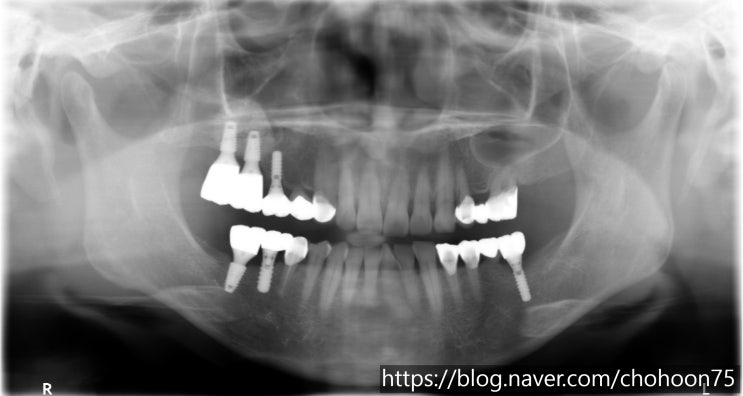

[조훈치과] 상악동 거상술(Sinus elevation)을 동반한 뼈이식 임플란트 치료 증례

안녕하세요. 조훈 치과입니다. 오늘은 조훈 치과에서 진행된 상악동 거상술을 동반한 뼈이식 임플란트 치료...